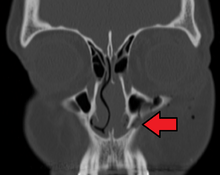

Maxilla

The maxilla (plural: maxillae /mækˈsɪliː/)[2] is the upper jawbone formed from the fusion of two maxillary bones. The upper jaw includes the palate of the mouth.[3][4] The two maxillary bones are fused at the inter maxillary suture. This is similar to the mandible (lower jaw), which is also a fusion of two mandibular bones at the mandibular symphysis.

The maxillary sinus appears as a shallow groove on the nasal surface of the bone about the fourth month of development, but does not reach its full size until after the second dentition.

The maxillary sinus presents the appearance of a furrow on the lateral wall of the nose. In the adult the vertical diameter is the greatest, owing to the development of the alveolar process and the increase in size of the sinus.